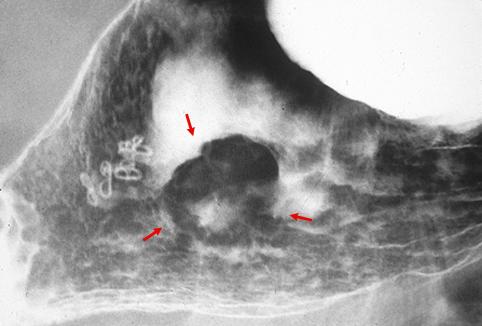

疾患(病理主体)の分類悪性上皮性腫瘍/腺癌

部位(臓器別)胃(部位)/体部

検査方法X-P

腫瘍の肉眼分類0型(表在型)/IIa型(IIa+IIc)

病変の最大径(ミリ)25〜29

腫瘍の深達度sm

多発腫瘍(同一臓器)有(異時性)